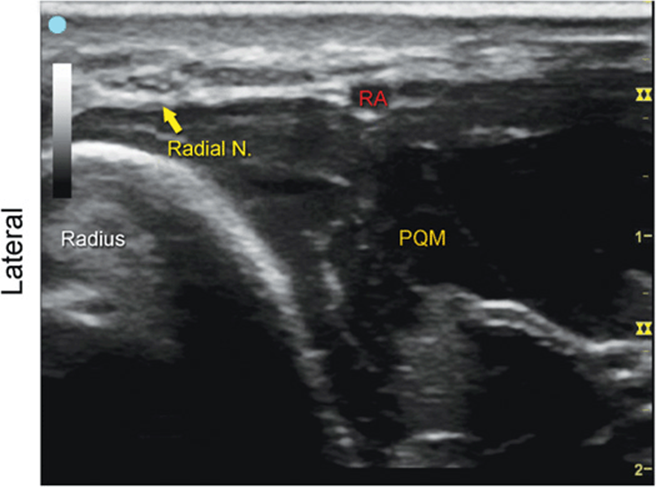

Radial Nerve

FIGURE 7.30.1A Ultrasound transducer position to image the radial nerve.

FIGURE 7.30.1B Ultrasound image of the radial nerve.

FIGURE 7.30.1C Labeled ultrasound image of the radial nerve.

FIGURE 7.30.1D Labeled cross-sectional anatomy of the radial nerve.

Abbreviations: RA, Radial Artery; PQM, Pronator Quadratus Muscle; FPLT, Flexor Pollicus Longus Tendon; FCRT, Flexor Carpi Radialis Tendon; APLT, Abductor Pollicis Longus Tendon.